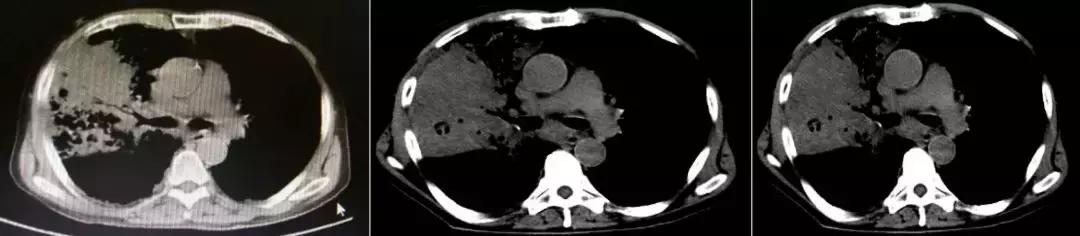

1天前急救车于我院急诊,血常规提示白细胞明显升高,胸部CT(2017-3-15):两肺感染,右肺上叶中叶膨胀不全,两肺间质改变,两肺肺气肿;急诊给予「头孢哌酮舒巴坦联合万古霉素」抗感染治疗,面罩10L/分吸氧维持血氧饱和度在85~95%之间,现为进一步诊治以「重症肺炎」收住我科。

CT:2018-3-15

既往有高血压病,患高血压10余年,平日未监测血压,最高达170/100mmHg,未规律服用降压药,血压控制差。2年前诊断结肠癌,行手术治疗,术后化疗6个疗程(具体用药不详),结肠癌术后逐渐出现活动后呼吸困难,并进行性加重,未诊治。吸烟40余年,1~2包/日,戒烟2年;家族史无特殊。